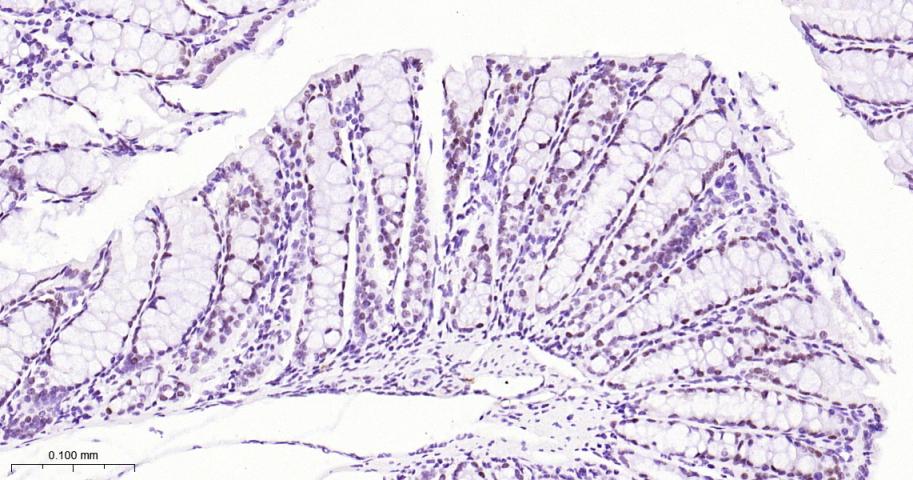

Paraformaldehyde-fixed, paraffin embedded Human Colon Cancer; Antigen retrieval by boiling in sodium citrate buffer (pH6.0) for 15 min; Antibody incubation with SATB2 Monoclonal Antibody, Unconjugated(bsm-62976R) at 1:200 overnight at 4°C, followed by conjugation to the bs-0295G-HRP and DAB (C-0010) staining.

Paraformaldehyde-fixed, paraffin embedded Mouse Colon; Antigen retrieval by boiling in sodium citrate buffer (pH6.0) for 15 min; Antibody incubation with SATB2 Monoclonal Antibody, Unconjugated(bsm-62976R) at 1:200 overnight at 4°C, followed by conjugation to the bs-0295G-HRP and DAB (C-0010) staining.

Paraformaldehyde-fixed, paraffin embedded Rat Colon; Antigen retrieval by boiling in sodium citrate buffer (pH6.0) for 15 min; Antibody incubation with SATB2 Monoclonal Antibody, Unconjugated(bsm-62976R) at 1:200 overnight at 4°C, followed by conjugation to the bs-0295G-HRP and DAB (C-0010) staining.